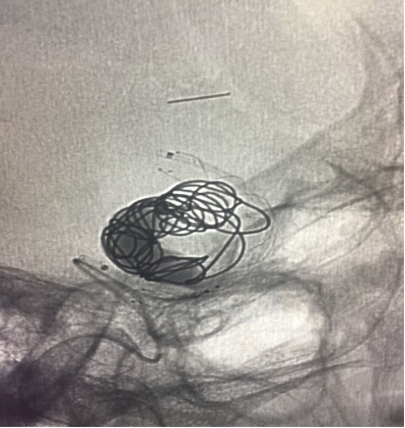

已可见流出道造影剂滞留,希望以后有血栓形成

进一步填塞,但可以看到下方支架打开不满意